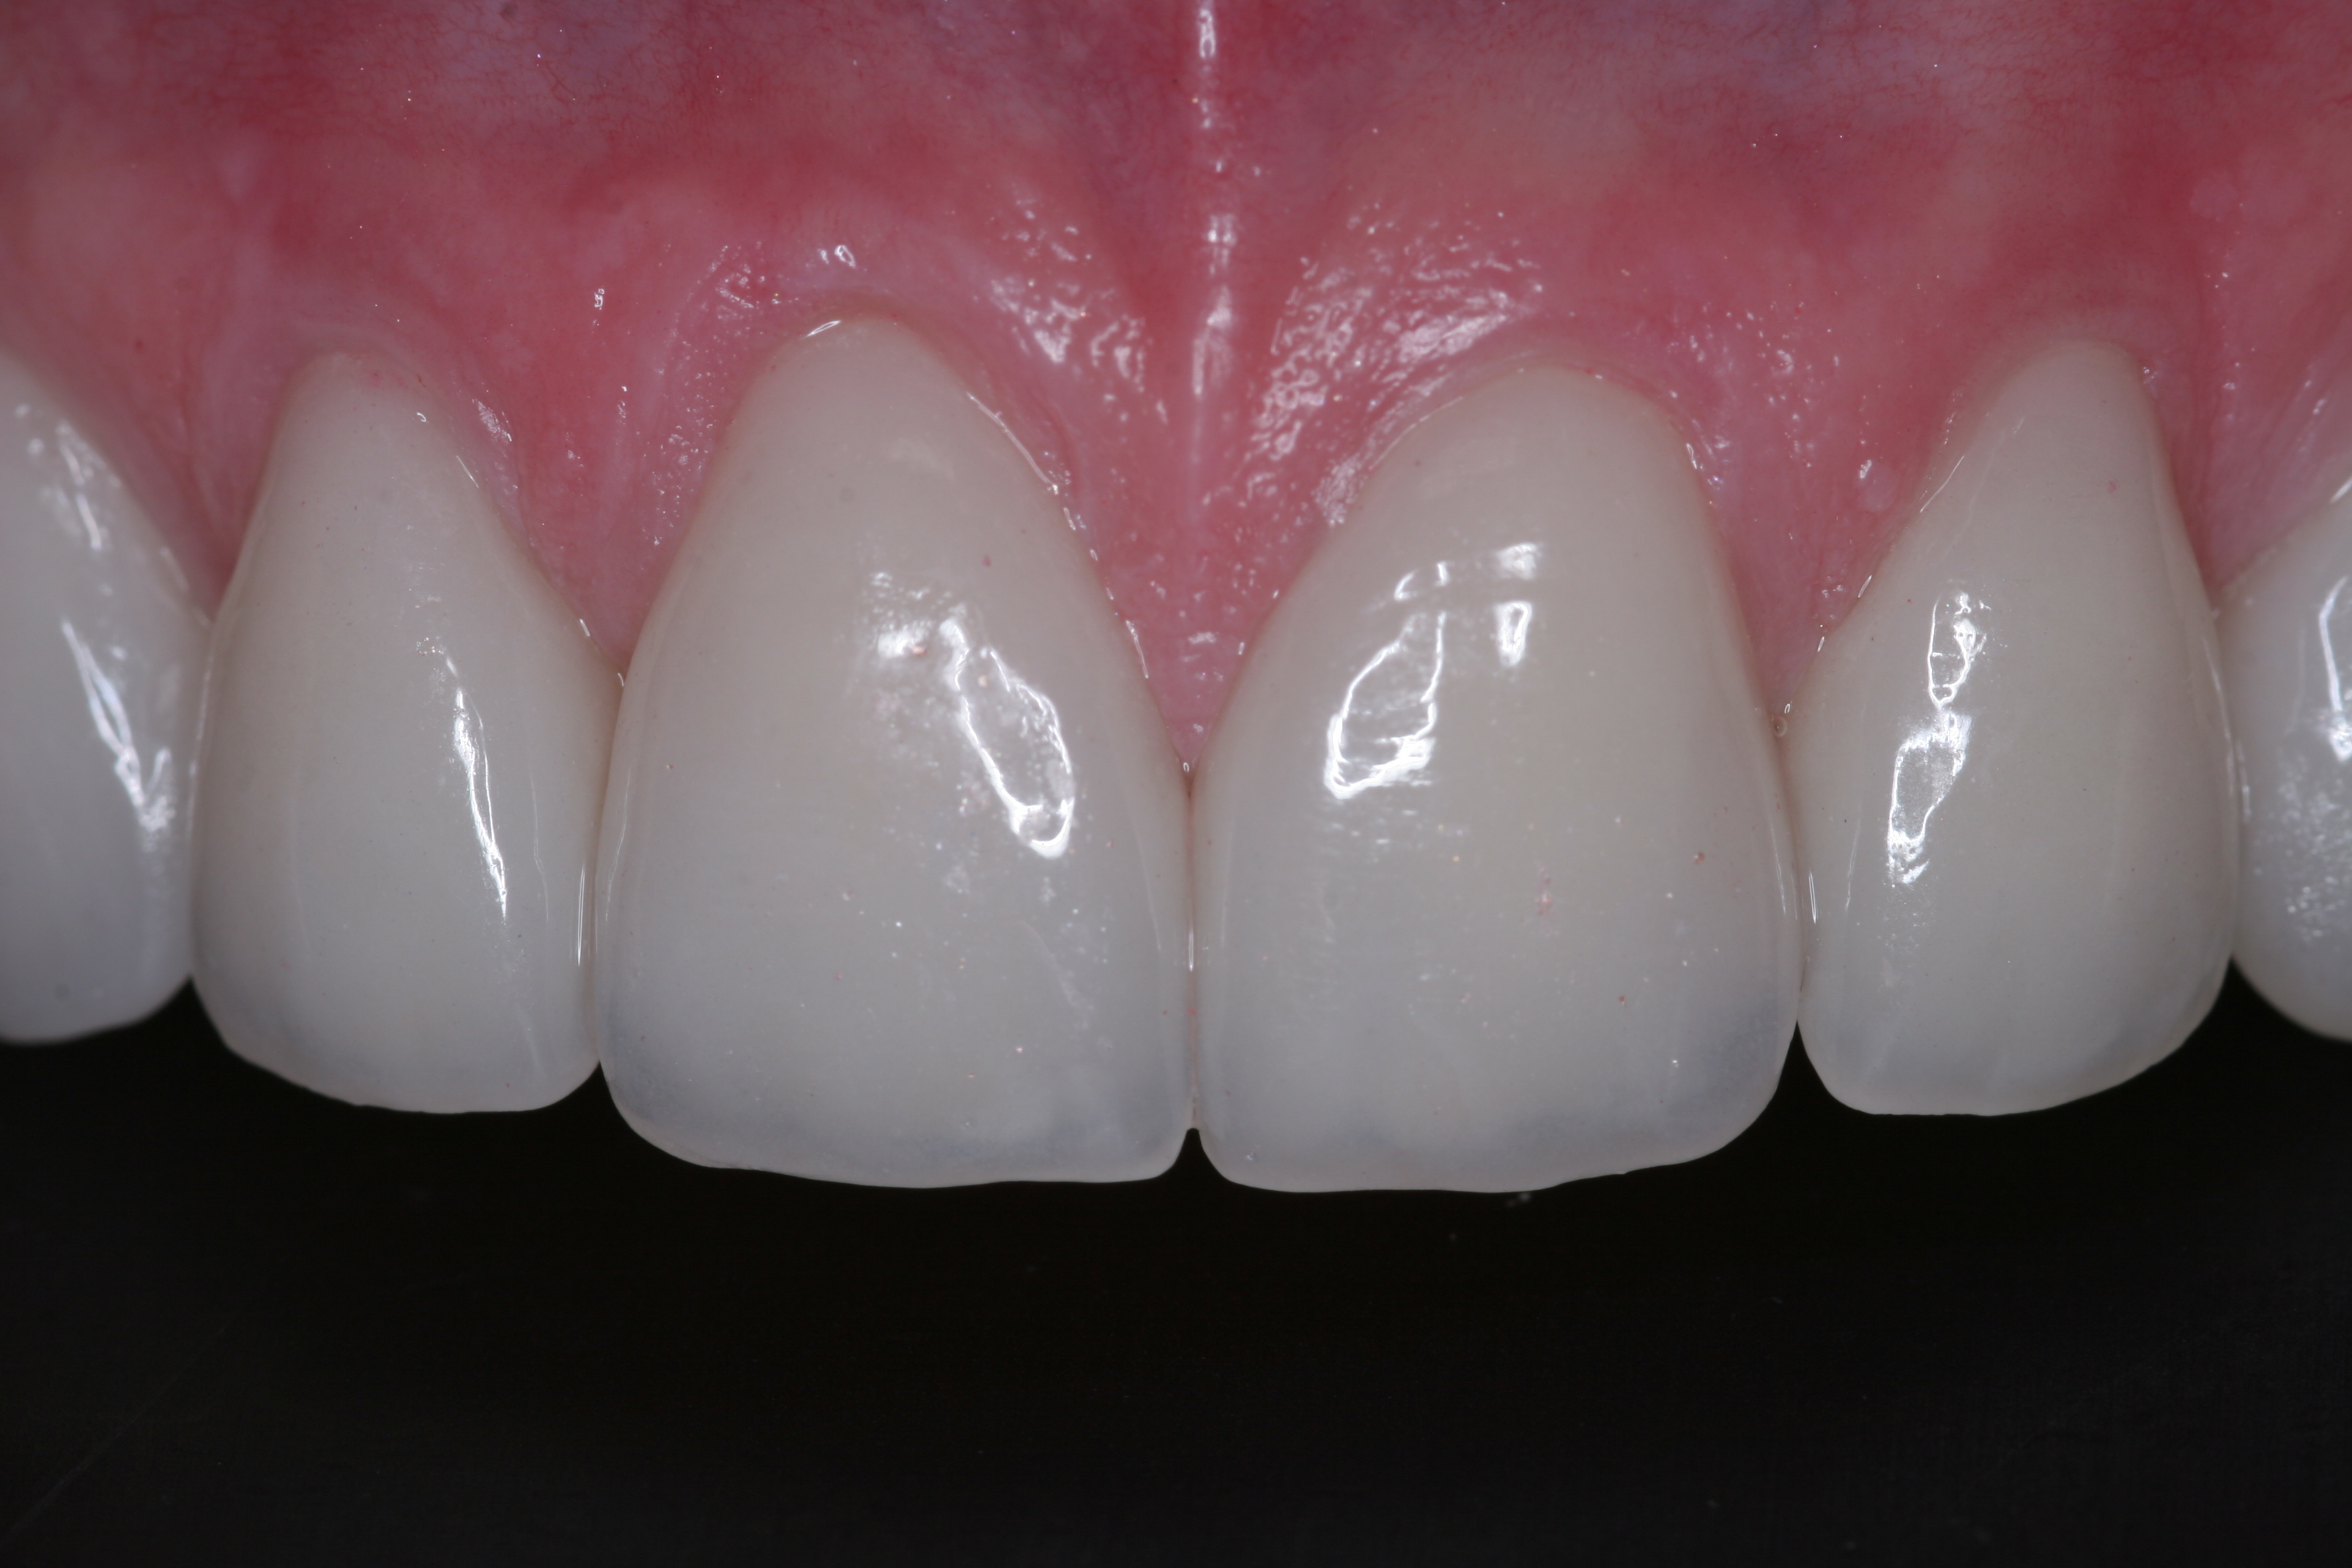

(22.) The final restorations, which reflect the changes modeled through the provisional phase.

Figure 22

(23.) The final restorations, which reflect the changes modeled through the provisional phase.

Figure 23

(24.) The final restorations, which reflect the changes modeled through the provisional phase.

Figure 24

(25.) The final restorations, which reflect the changes modeled through the provisional phase.

Figure 25

(26.) The final restorations, which reflect the changes modeled through the provisional phase.

Figure 26

(27.) The final restorations, which reflect the changes modeled through the provisional phase.

Figure 27

(28.) The final restorations, which reflect the changes modeled through the provisional phase.

Figure 28

(29.) The final restorations, which reflect the changes modeled through the provisional phase.

Figure 29

Once approved, impressions of the provisionals were taken so the laboratory could precisely copy the 3D position of the anterior teeth as successfully proven in the provisionals. The postoperative result and final functional photographs are shown in Figure 22 through Figure 29. Posterior treatment can now be completed in segments as necessary. Posterior morphology will be developed in harmony with the now corrected anterior contour and functional parameters. The fulfillment of the previously mentioned requirements of occlusal stability were evaluated and refined in the final restorations. The patient was placed in a posttreatment dual-arch B splint appliance to help manage any further parafunctional forces should they occur.